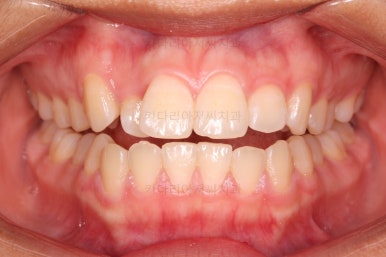

치열이 매우 바르게 되었고 교합도 양호하며 뻗쳐 있던 앞니 각도도 좋아졌네요.

돌출의 느낌도 처음보다 많이 좋아졌어요.

웃을 때 보이는 치열의 느낌도 좋고요.

전후 사진을 비교해 볼게요.

입술의 두께로 인한 돌출감 개선에 약간은 한계가 있었지만 그래도 본인이 만족한 수준에서는 돌출감을 개선했고 치열도 매우 가지런하게 마무리를 할 수 있었답니다.